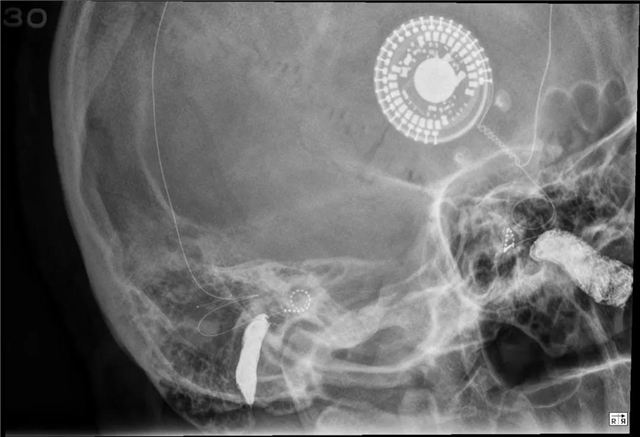

人生就是如此,与其尽量隐蔽自己,不如敞开胸怀展示真正的自己。助听器和人工耳蜗不仅可以简约大气,也能“酷炫非凡”,希望这些图片能给大家不同的想象。